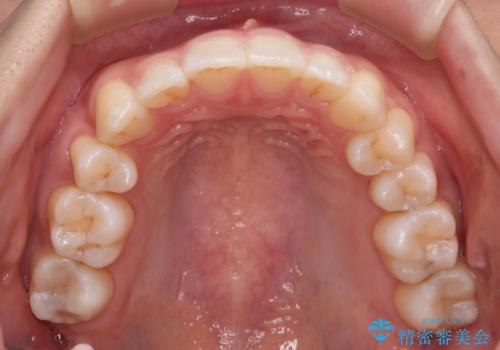

【審美装置】八重歯気になる

- 八重歯と叢生を主訴に来院されました。なるべく健康な歯を残したいという患者様の希望から、右側上下4番抜歯をしてワイヤー矯正する治療計画を立てました。

なるべく健康な歯を残したいという患者様の希望から、右側上下4番抜歯をして矯正しました。片側抜歯だったため、正中がズレないように気をつけながら治療を行いました。

正中もズレることなく主訴である八重歯と叢生を改善することができました。

患者様の満足度も高く治療を終えられました。